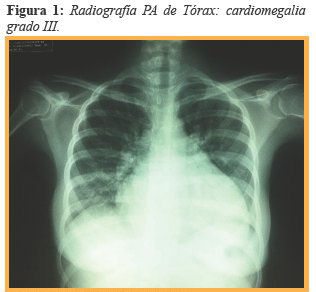

A su ingreso se ordenaron estudios de química sanguínea (Ver tabla 1) y estudios de imagen en los que la radiografía de tórax (Figura 1) mostró un índice cardiotorácico de 0,61 representando una cardiomegalia grado III.